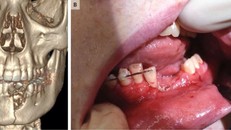

Thuốc lá điện tử phát nổ trong miệng, cậu bé 17 tuổi bay răng, gãy đôi xương hàm

Khi đang hút thuốc lá điện tử, không may điếu thuốc phát nổ khiến cậu bé 17 tuổi bị gãy đôi xương hàm, bay mất răng và mồm không thể khép lại.